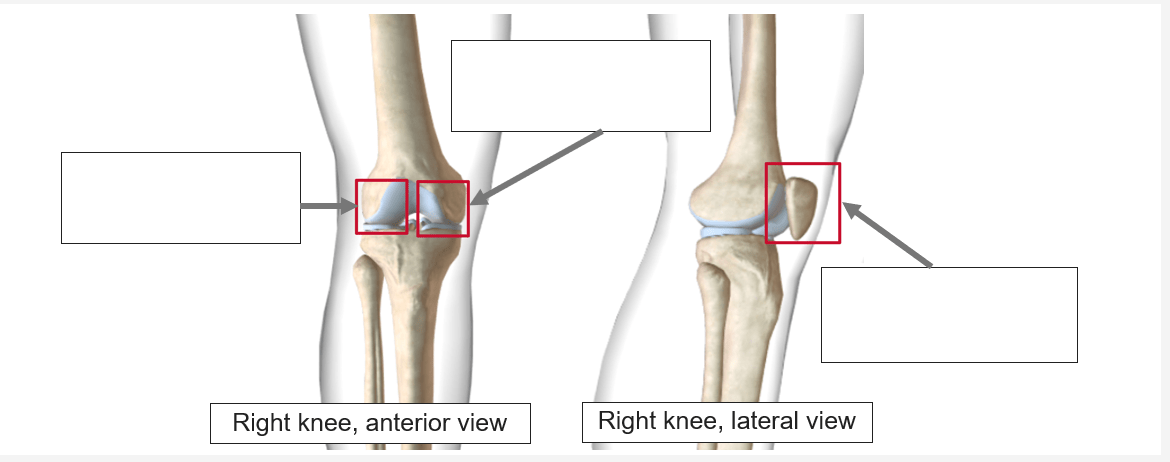

Name 3 compartments of Knee

Lateral tibiofemoral ligament

Medial tibiofemoral ligament

Patellofemoral ligament

...............increases the surface area of the tibiofemoral joint, aids in shock absorption, and helps guide femoral movement.

Meniscus